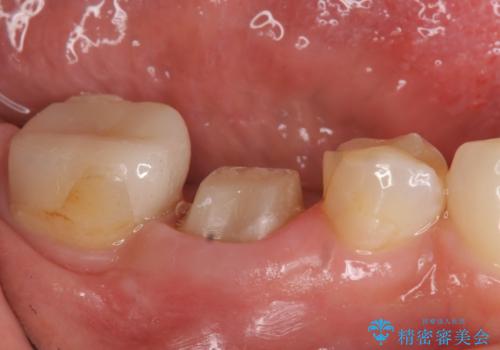

- たまに疼くことがあると他院を受診したところ抜歯を勧められたが、歯を残せないものかと当院にいらっしゃった方の症例です。

診査の結果抜歯の必要性はなさそうだったため再根管治療を行い、その後オールセラミッククラウンによる補綴を行いました。